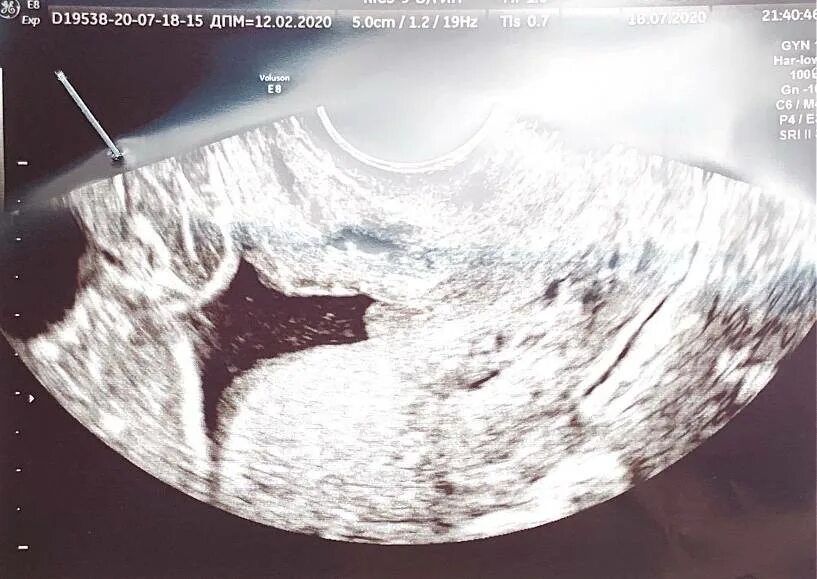

Внутренний зев воронкообразно